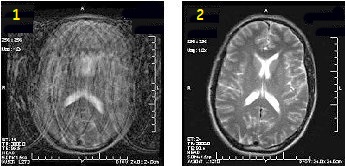

Brain applications

Use PROPELLER to significantly reduce patient motion artifact due to the oversampling of k-space center. The oversampling allows for checking raw data inconsistencies and performing motion correction to the reconstruction process. The result is high SNR and CNR with a slight resolution loss, and reduced motion artifact. It improves SNR and CNR compared to traditional FSE with comparable scan time and it reduces motion artifact.

Figure 1. Motion reduction comparison

Table 1. Image legend

Number

Description

1

FSE image

2

PROPELLER T2 image